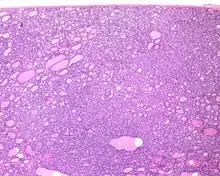

Several specific features must be identified for the tumor to be classified in this new category, while exclusion criteria should also be evaluated.

1) Encapsulated or partially encapsulated. The tumors are usually very well delimited or circumscribed, with the majority encapsulated, surrounded by a well formed fibrous connective tissue capsule.

2) Complete absence of invasion of any kind in a tumor that has been thoroughly and carefully evaluated with the whole capsule of the lesion sampled.

3) Predominantly follicular pattern of growth. Papillary structures should not be present. Further, solid, insular, or trabecular architecture must be <30% of the overall tumor for this category to still apply. Colloid (the material that thyroid follicular cells create) is easily identified throughout.

4) Must have the characteristic nuclear features of papillary thyroid carcinoma, although sometimes the features are patchy in distribution without all of the tumor showing those features. The nuclear features can be divided into three main categories:

- Nuclear size and shape: nuclear enlargement, nuclear elongation, and nuclear overlapping and crowding. Loss of nuclear polarity, with nuclei at the lumen, middle, or basal zone of the cells is also a helpful finding.

- Nuclear membrane irregularities: irregular nuclear contours, nuclear grooves and folds, "rat-bites" or demi-lune formations, and the presence of intranuclear cytoplasmic inclusions.

- Nuclear chromatin characteristics: nuclear chromatin clearing, often with condensation or margination along the nuclear membranes, resulting in accentuated nuclear margins, glassy nuclei, or fine, even delicate, powdery nuclear chromatin.

- ↑ Image by Mikael Häggström, MD. Reference for findings: Rachel Jug, M.B.B.Ch., B.A.O., David Poller, M.D., Xiaoyin "Sara" Jiang, M.D. "NIFTP". Pathology Outlines.